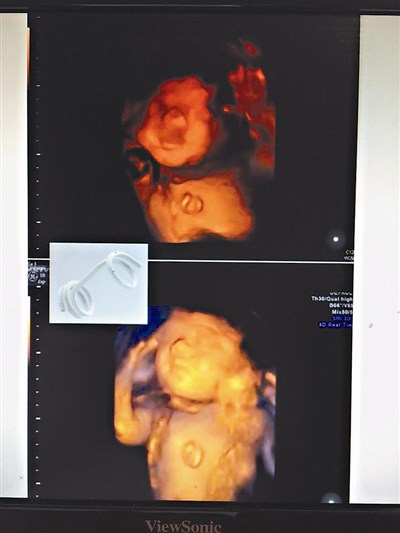

林口長庚醫療團隊利用超音波定位,將支架放在胎兒的體內,助胸水引流到羊水內。圖/陳雨鑫

長庚醫療團隊完成胎兒胸腔引流管置放術,是經由超音波指引,將長針放入孕婦腹腔,經由子宮、羊水腔,進入胎兒的胸腔,把引流管置放在胸腔內,將胸水引流到羊水腔,手術過程只要幾分鐘。